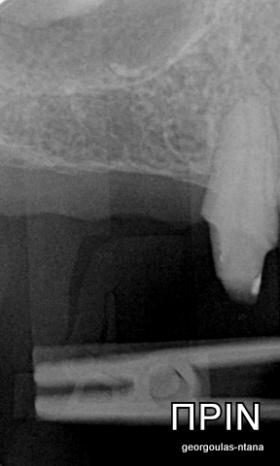

ΠΡΟΣΘΕΤΙΚΗ ΑΠΟΚΑΤΑΣΤΑΣΗ ΣΤΗΝ ΑΝΩ Κ ΚΑΤΩ ΓΝΑΘΟ ΚΑΙ ΤΟΠΟΘΕΤΗΣΗ ΕΜΦΥΤΕΥΜΑΤΩΝ ΜΕ ΚΛΕΙΣΤΗ ΑΝΥΨΩΣΗ ΙΓΜΟΡΕΙΟΥ

Ο ασθενής  προσήλθε στο ιατρείο μας θέλοντας να βελτιώσει την εμφάνιση των πρόσθιων δοντιών του και να αποκαταστήσει την υγεία κ την λειτουργία όλου του στόματος. Πραγματοποιήθηκε περιοδοντική θεραπεία κ ενδοδοντικές θεραπείες (απονευρώσεις) όπου κρίθηκε απαραίτητο και στη συνέχεια τοποθετήθηκαν 3 εμφυτεύματα, 2 δεξιά στις θέσεις του πρώτου κ δεύτερου γομφίου κ 1 αριστερά στη θέση του πρώτου προγομφίου. Κατά την  τοποθέτηση των 2 εμφυτευμάτων της δεξιάς πλευράς, πραγματοποιήθηκε κλειστή ανύψωση ιγμορείου με το σύστημα Piezotome-Intralift , τεχνική που εξασφαλίζει τη μικρότερη δυνατή επέμβαση κ τη μικρότερη μετεγχειρητική ταλαιπωρία (minimally invasive), καθώς κ αυξητικους παράγοντες PRF. Σε όλη τη διάρκεια της θεραπείας  ο ασθενής ήταν καλυμμένος τόσο αισθητικά όσο και λειτουργικά με προσωρινές μεταβατικές αποκαταστάσεις. 4 μήνες μετά την  τοποθέτηση των εμφυτευμάτων κ την οστεοενσωμάτωσή τους, ακολούθησε η τοποθέτηση των μόνιμων αποκαταστάσεων.